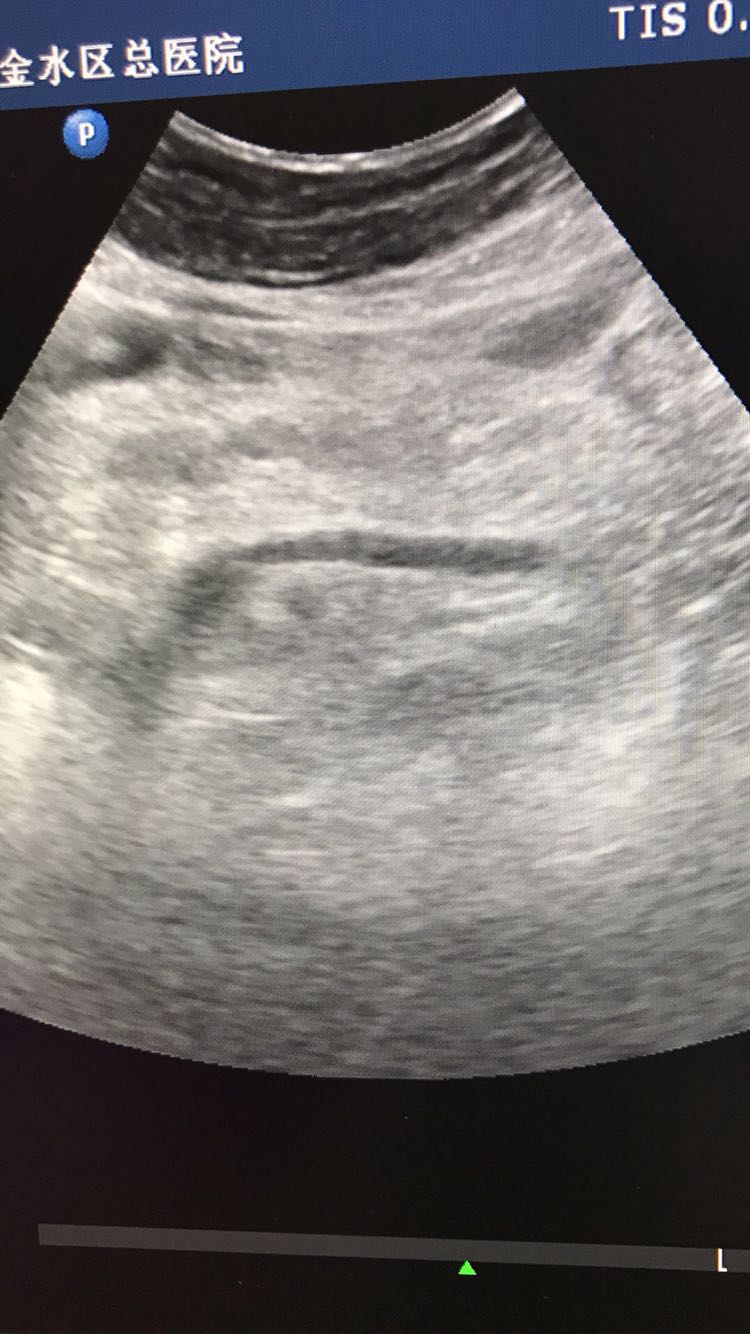

胰腺体积大

患者体检发现

查体 辅查

建议结合临床及其他相关实验室检查